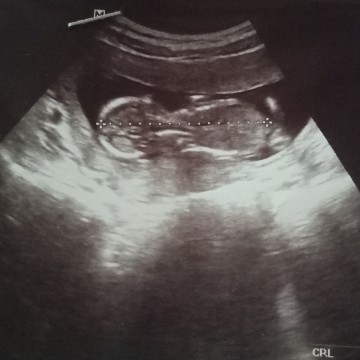

อัลตร้าซาวต์

อายุครรภ์13สัปดาห์ค่ะ แต่เด็กเป็นตัวชัดเจนมาก มีแม่ๆคนไหนซาวต์แล้วชัดแบบนี้บ้างค่ะ

บ้านนี้ตอน13wค่ะ ให้หวยด้วยค่ะ